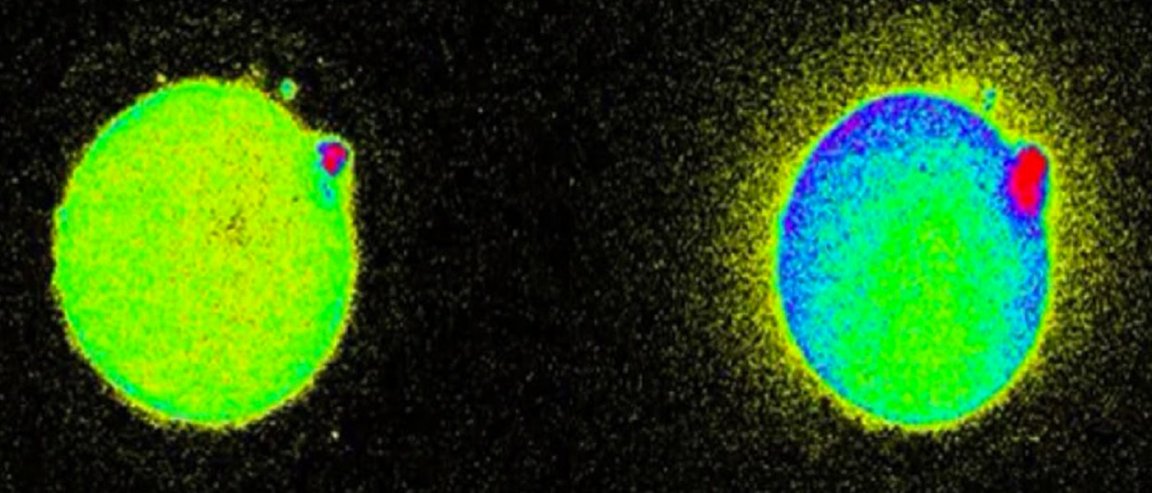

The egg cells apparently flash when pierced by sperm, as this triggers calcium levels to rise inside the egg, and prompts the release of zinc. The zinc then binds to molecules that emit a fluorescence which camera microscopes can pick up.

The zinc sparks continue like a symphony for about two hours from conception. “As the zinc shoots out, it binds to small molecules which emit a fluorescence, which can be picked up by camera microscopes,” states Sarah Knapton.

The brighter the egg sparks in reaction to sperm enzyme, the more viable the egg.